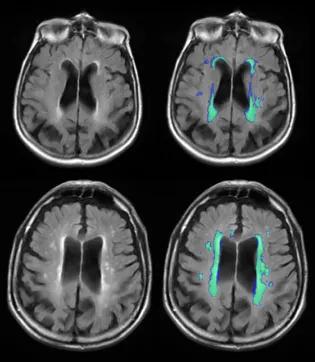

At The Row Fogo Centre for Research into Aging and the Brain, we are dedicated to improving understanding of the brain damage caused by small vessel diseases (SVD) Although SVDs have been recognised to be a main cause of age-related brain diseases such as stroke, dementia and Alzheimer’s disease, there is still very limited understanding of this common disease.We study people to understand how SVD starts and affects them. We use sophisticated medical imaging methods such as magnetic resonance imaging (MRI) to find out about how SVD is affecting the brain and blood vessels. To extract information from the brain MRI, we have developed highly specialised computer methods to analyse the images. The medical analysis tools and image databanks from our studies allow us to improve early detection and diagnosis of SVDs, identify causes and the consequences of SVDs, and to develop methods for prevention and treatment of small vessel diseases (SVDs). Moreover, our research discoveries contribute to advancing understanding other common disorders such as Multiple Sclerosis and Motor Neuron Disease.The Row Fogo Centre for Research into Aging and the Brain aims to promote early career researchers by supporting the development of their research skills in the field of cerebral SVD. With a specific focus on the young researchers, The Row Fogo Centre holds workshops, provides lectures in image analysis, and advice and training. The Row Fogo Centre sponsors events at the University of Edinburgh to exchange knowledge and promote the scientific work of all who are interested in SVDs. Methods developed at the Row Fogo Centre are incorporated into the Imaging MSc, other training programmes and short online courses for future generations of medical professionals. Related links Row Fogo Centre Research Projects Ways to fundraise or make a donation to support our research Impact of your donations on our research Image analysis tools (external link) Training programmes and short online courses in medical imaging (external link) This article was published on 2024-08-27